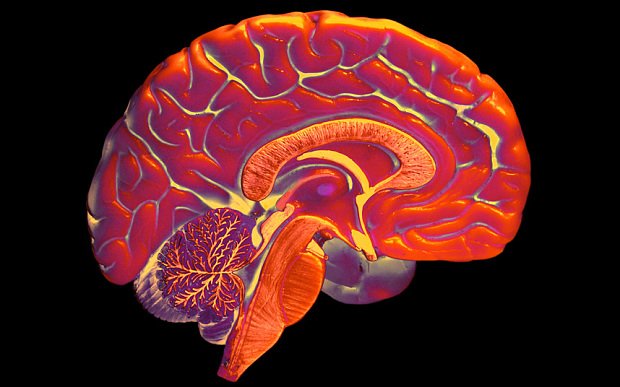

Universities should insist that students learn a second language as part of their degree to help prevent dementia in later life and broaden their horizons, a language expert has claimed. Professor Antonella Sorace, founder of the Bilingualism Matters Centre at Edinburgh University, said there was now good evidence to show that bilingualism could protect the brain in later life. Studies …